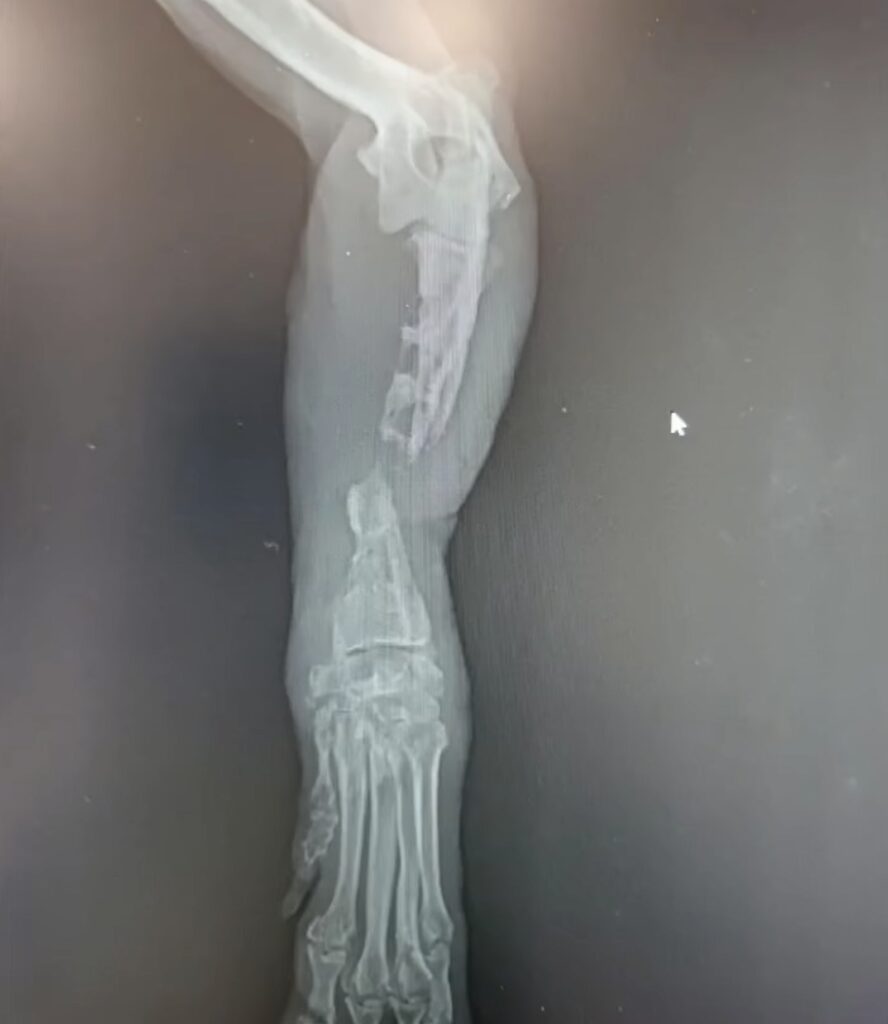

Teď k úkonům: Štěpánek na obou končetinách byly fragmenty kostí fixované rekonstrukční ploténkou, aby se zastabilizovala fraktura. Defekty v kostech a chybějící části byly vyplněny směsí: jeho krev, žebro (13. žebro), kostní dřeň a materiál ossa base. V obou končetinách byly v kostech velké defekty, které byly způsobeny infekcí z těch externích fixatorů. Hrozí riziko, že se implantáty vlivem výrazné atrofie kostí neuchytí. Prognóza: zadní lepší.